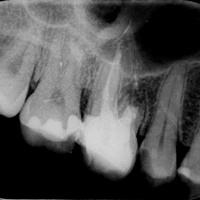

Pacjent z bólem, nieudana próba udrożnienia kanałów pod mikroskopem. Decyzja o resekcji korzenia policzkowego dalszego. RTG kontrolne rok po zabiegu.